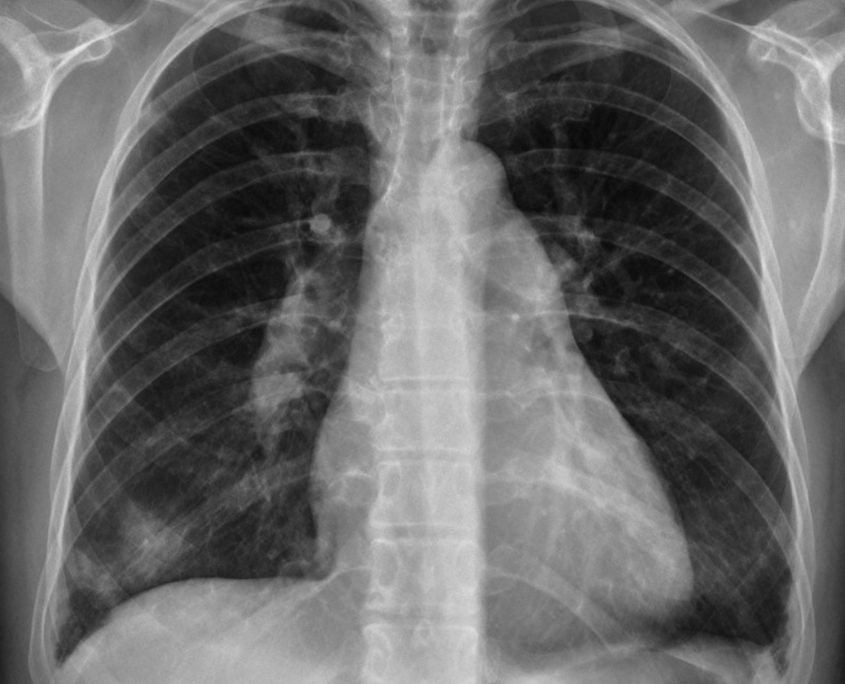

Radiographie thoracique qui montre un pneumothorax bilatéral de grande Scanner Thoracique Youtube Le patient est allongé sur la table d'examen. Le scanner thoracique est un examen #radiologique sur le #thorax qui est réalisé à l’aide d’un appareil de scanner. Le scanner thoracique permet d’obtenir des images précises dites en coupe du thorax. Voici une vidéo explicative des pratiques réalisées en ct scanner lors d'un examen. Pleuropneumopathie droite avec toux expectoration. Comment se. Scanner Thoracique Youtube.